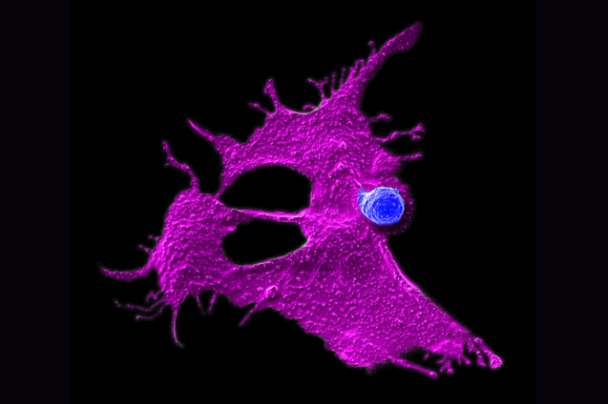

UCLA 研究人员发现,将树突状细胞疫苗与免疫增强剂联合使用,可显著提升机体对抗恶性胶质瘤的能力,如同为免疫系统注入一剂强心针。

UCLA Health 的研究团队利用捐献的造血干细胞,成功批量培养出增强版 CAR-NKT 细胞,实现常备存储、即时使用。

在三阴性乳腺癌研究中,团队通过多重识别机制,同时攻击多个肿瘤标志物,形成”多点合围”,有效防止肿瘤通过单一标志物改变而逃逸。